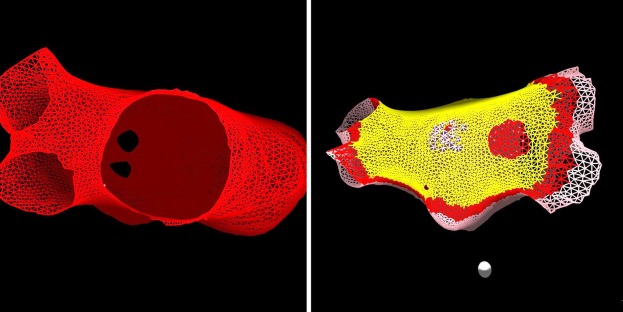

The Interactive Left Atrium Model is a GPU-accelerated N-body computational simulation that enables real-time, interactive exploration of cardiac arrhythmias. Implemented in CUDA C++ with OpenGL visualization, this project combines physics-based cardiac muscle modeling with interactive ablation capabilities for both research and medical education.

Our model uses an N-body simulation approach where individual nodes represent cardiac muscle cells (myocytes) connected by virtual muscle fibers. These connections allow electrical signals to propagate through the tissue, mimicking how real heart muscle conducts impulses. The model captures both electrical activation and mechanical contraction, enabling users to observe and manipulate cardiac behavior in real-time. This interactive framework makes it possible to induce arrhythmias and test virtual ablation strategies.

Idealized LA (13,000 nodes)

Anatomical features: pulmonary veins, mitral valve, Bachmann's bundle. Tests realistic geometry before patient data.

Patient-Specific LA

Real left atrial geometries from medical imaging (CTA, MRI). Clinically relevant models for arrhythmia reproduction and ablation planning.

The digital twin successfully reproduced multiple clinically relevant arrhythmia mechanisms observed in patients. By adjusting conduction velocities and applying precisely timed ectopic events, we induced various forms of reentrant activity including micro-reentry, macro-reentry, and atrial flutter. These arrhythmias demonstrated self-sustaining propagation patterns consistent with clinical observations.

Arrhythmia Induction

We successfully induced left atrial flutter by slowing conduction velocity between pulmonary vein openings and triggering ectopic events at specific locations and times. Reentrant circuits and rotors emerged naturally, producing sustained activation patterns that resembled those seen in real patients.

Virtual Ablation

Simulated catheter ablation reliably terminated reentrant activity and restored organized conduction patterns. We successfully eliminated induced flutters using virtual ablations, allowing the system to return to normal rhythm. The model demonstrated effectiveness on both idealized and patient-specific atrial geometries.